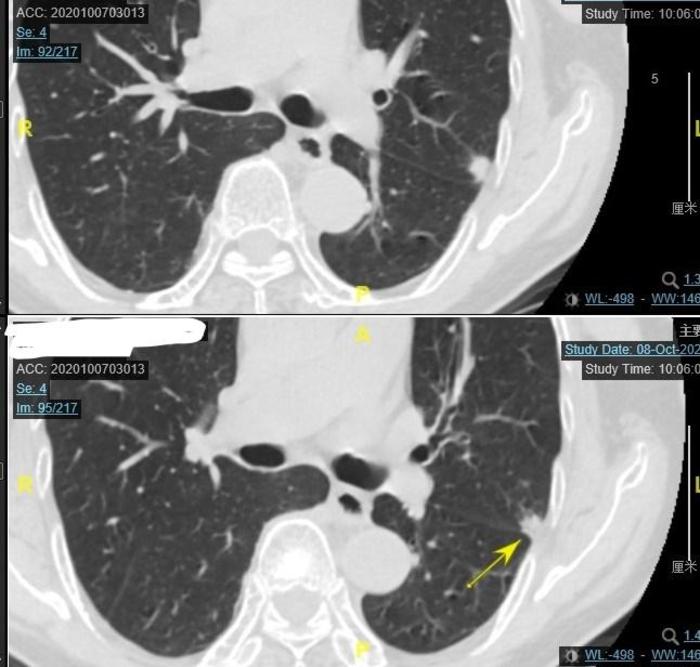

有一个老太太,2018年3月发现左下肺一个混合磨玻璃结节,当地医院和南京市的**医院两年来一直考虑是良性的。

上图可见蓝色箭头指示的2018年3月左下肺混合磨玻璃结节,大小约20毫米,实性成分为主,照片上结节内部有一些发暗的的小缝隙,使这个混合磨玻璃结节看起来像一个洋葱头。这是一个混合磨玻璃结节,但是当时接诊的医生由于水平有限,认为是慢性炎症,没有认出这个结节其实是一个实性成分为主的混合磨玻璃结节。

上图可见蓝色箭头指示的2019年7月左下肺混合磨玻璃结节,可见仍然为20毫米,变化不大。

两年期间曾经静脉抗炎,结节无变化。

上图为今年9月份住院后的CT,由两张CT组成。上面的CT的蓝色 箭头指向的是左上肺实性结节。下面的CT黄色箭头指向的是这个结节紧贴斜裂,好像比两年半前大了1毫米,差别不大。

上图为今年9月份住院后的CT,由两张CT组成。上面的CT的蓝色 箭头指向的是左上肺混合磨玻璃结节。下面的CT黄色方框是这个结节的最高CT值-281,大小与两年半前比变化不大。应该是一个早期肺癌。